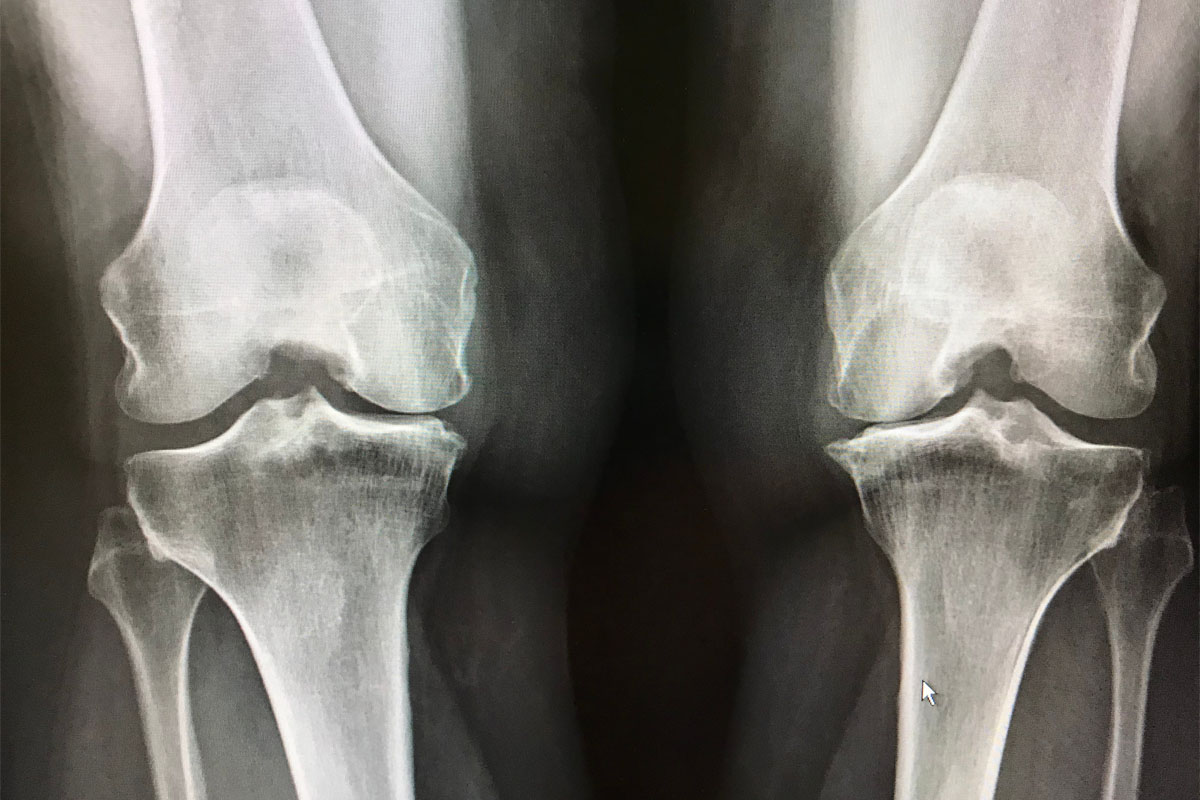

Osteoarthritis is the most extensive type of arthritis, affecting millions of people across the globe. It transpires when the preventive cartilage that pads the ends of the bones becomes worn over time.

Despite the fact that osteoarthritis can be damaging to any joint, the disease most commonly affects joints in the knees, hands, hips, and spine.

Osteoarthritis transpires when the cartilage that pads the end of bones in your joints after a while deteriorate. Cartilage is a set, slippy tissue that allows nearly frictionless joint motion.

After a while, should the cartilage wear down completely, bone is going to rub on bone.

This is sometimes known as a “wear & tear “ailment. But apart from the breakdown of cartilage, osteoarthritis changes the whole joint. It is going to make changes in the bone and weakening of the joining tissues that hold the joints together and connects muscle to bone. It also produces swelling to the joints lining.